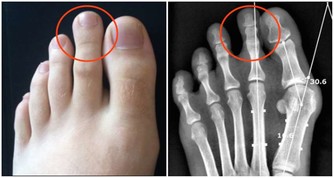

1、喝酒容易臉紅的人

研究表明,酒精在人體內的代謝要通過乙醛脫氧酶2(ALDH2)來完成,

人體內的乙醛脫氧酶2能將乙醛氧化為無致癌作用的乙酸,

最終分解成對人體無害的二氧化碳和水排出體外。

但當乙醛脫氧酶2正常基因發生變異之後,會使該酶失去活性,

從而導致飲酒後血中的乙醛濃度增高6倍多,

長期酗酒,體內的乙醛就會蓄積,最終可能導致肝癌發生。